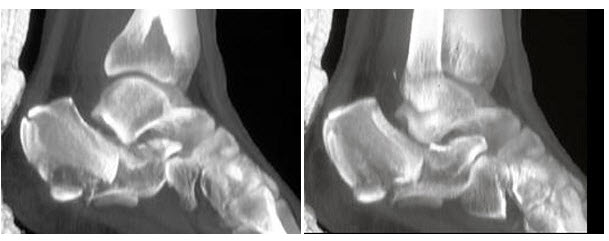

68、单项选择题

男,17岁,踝关节疼痛,关节作响,结合图像,最可能的诊断是()

A.骨结核

B.剥脱性骨软骨炎

C.退行性骨关节病

D.骨髓炎

E.纤维性骨皮质缺损